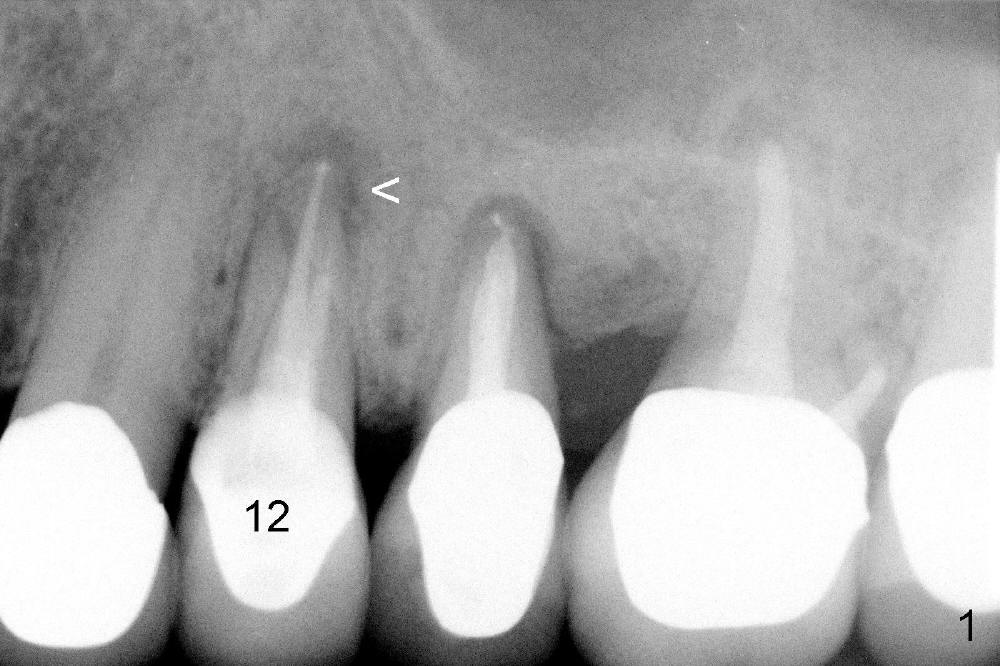

A 50-year-old man has mild pain in the upper left 1st bicuspid 3 years after root canal retreatment with placement of two posts (Fig.1). Findings of clinical exam are consistent with root fracture (Fig.2). Extraction reveals two fused roots (Fig.3,4). Probing indicates that the buccal plate is defective. Osteotomy is initiated in the palatal socket with a 2 mm pilot drill, followed by 2.5 and 3.0 mm reamers and 4.5x20 mm tap. The septum appears to have been pushed buccally (Fig.5 *) and form a new buccal wall (partially, strengthened by bone graft mentioned below) for the implant to be placed. The implant (4.5x20 mm) is placed in the palatal socket (Fig.6 *) with insertion of an abutment (A: 3.5x5 mm 0º), while a mixture of autogenous bone (harvested from reamers) and Synthograft (Bicon) is placed in the shrunken buccal socket (Fig.7; using allograft may decrease postop bony shrinkage). The bone graft is then contained by an immediate provisonal without collagen membrane or flaps. The patient is doing well postop. The gingiva is healthy (Fig.8*) when the provisional is removed 3 months postop with normal papillae (Fig.9 arrowheads). It remains the same 1 month post cementation (Fig.10,11). For further follow up, see immediate implant of the tooth #13.